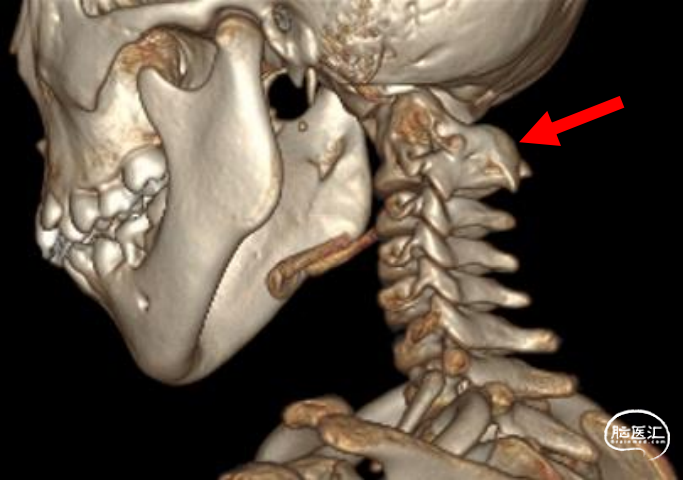

先天性寰枕畸形主要是指枕骨底部、寰椎及枢椎发育异常先天发育异常并伴有神经系统和软组织发育异常的一种先天性颅骨疾病, 它包括扁平颅底、颅底陷入、寰椎融合、颈椎分节不全、寰枢椎脱位、小脑扁桃体下疝畸形等多种多样的畸形,有时还可出现第2、3 颈椎畸形融合, 颈椎缺数及颈部脊椎屈曲畸形等,常合并脊髓空洞。如果患者存在寰枢椎关节脱位并且合并两种以上的畸形,则称为复杂寰枕畸形,约占先天性寰枕畸形的18%。临床表现主要以四肢乏力、头晕、偏身感觉、运动障碍、共济失调、步态蹒跚、瘫痪、二便失禁等为主。术前完善颈椎X片、颈椎CT平扫+三维重建及全脊髓MRI对明确本病的诊断, 病情复杂性的评估, 及手术入路和手术方法的选择都有重要的意义。